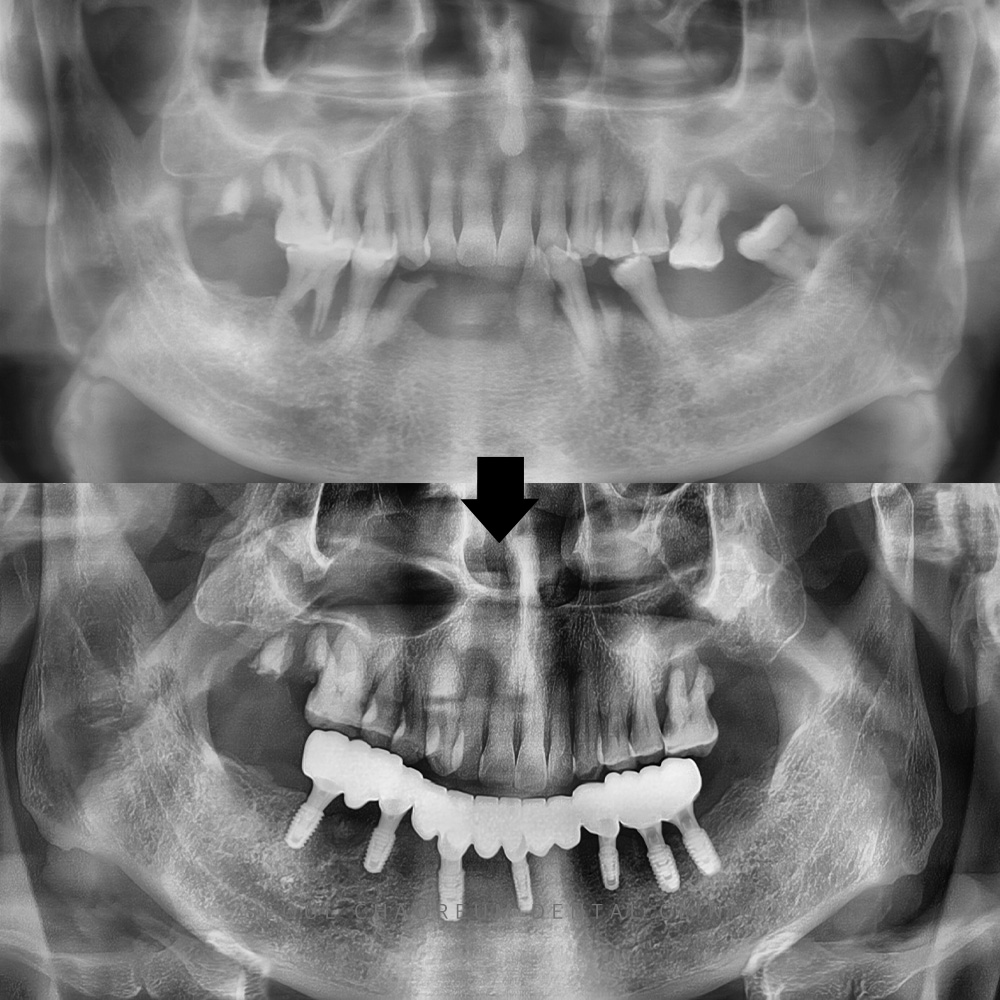

세교동치과 365서울차오름에서는

남아 있는 치아들의

예후가 좋지 않아 치료를 통해

살린다고 하더라도

빠른 시일 내에 탈이 날 가능성이 있어

발치 후 임플란트를 진행하기로

계획을 수립하였습니다.

먼저 전체적인 스케일링을 진행한 후,

오른쪽 아래 치아에는

큰 염증이 있었기 때문에,

발치하면서 염증 부위도

깨끗하게 소파하여 처리했습니다.

그 후, 임플란트 식립과 함께

뼈이식도 진행하였고,

이 작업이 마무리된 후에는

왼쪽 치아의 발치와 임플란트 식립,

뼈이식을 순차적으로 진행했습니다.

그리고 세교동치과 365서울차오름에서는

아래 임플란트를 식립하면서,

환자분이 빠르게 일상 생활을 할 수 있도록

임시 치아를 바로 장착했습니다.

25.03.21 / 25.07.06

치료 전후 사진입니다.